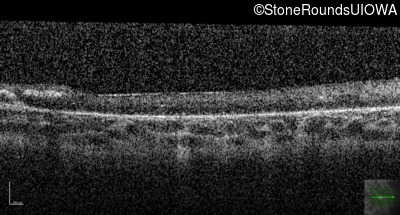

Optical Coherence Tomography - Left - Hand Motion sc

Exemplar